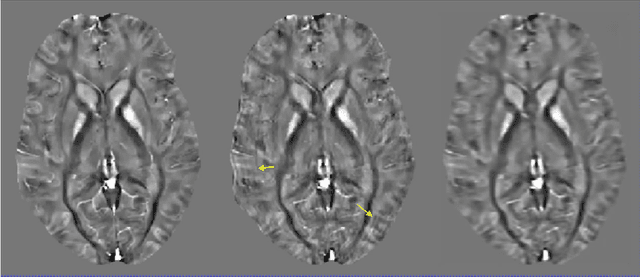

Abstract:Purpose: To develop a pipeline for motion artifact correction in mGRE and quantitative susceptibility mapping (QSM). Methods: Deep learning is integrated with autofocus to improve motion artifact suppression, which is applied QSM of patients with Parkinson's disease (PD). The estimation of affine motion parameters in the autofocus method depends on signal-to-noise ratio and lacks accuracy when data sampling occurs outside the k-space center. A deep learning strategy is employed to remove the residual motion artifacts in autofocus. Results: Results obtained in simulated brain data (n =15) with reference truth show that the proposed autofocus deep learning method significantly improves the image quality of mGRE and QSM (p = 0.001 for SSIM, p < 0.0001 for PSNR and RMSE). Results from 10 PD patients with real motion artifacts in QSM have also been corrected using the proposed method and sent to an experienced radiologist for image quality evaluation, and the average image quality score has increased (p=0.0039). Conclusions: The proposed method enables substantial suppression of motion artifacts in mGRE and QSM.